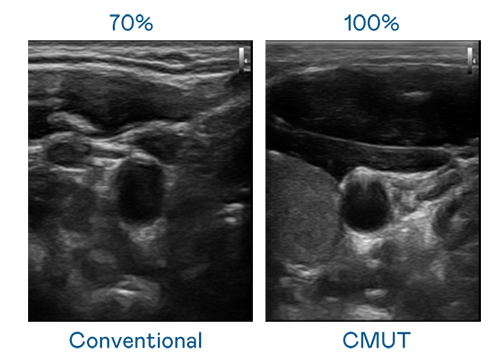

CMUT 技术是一种用电容式微机电元件来产生超音波讯号的技术。与传统 PZT 压电式技术相比,CMUT 频宽增加 30%,更宽频的超音波讯号让影像解析度大幅提升,是实现高影像品质医疗超音波扫描、促进精准医疗发展的关键技术。

超音波影像的解析度高低,首先取决于探头能发出的讯号频宽。人生就是搏尊龙 CMUT 可提供高清晰的超音波讯号,提供高频宽、高灵敏度、影像纹理细节更高的超音波影像,协助医护人员缩短影像判读时间及利用精准的医疗影像进行诊断。